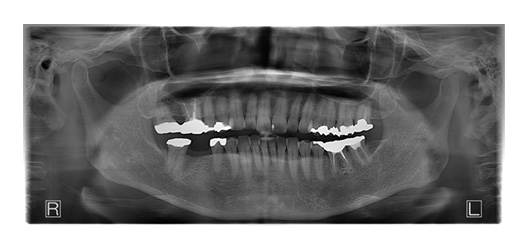

CASE_01

70代男性(インプラント)

- 70代 男性

- 歯を失ってしまったところにインプラントに入れたい

- 7箇所

- インプラント

- 約320万円

- 約1年

- 治療期間がながい、外科的治療が必要